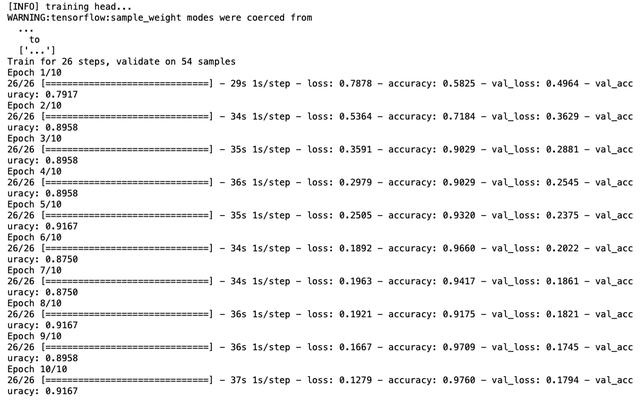

结果看起来已经相当有趣了,验证数据的精度达到了92%!绘制精度图表:

评估训练模型:

从用最初选择的超参数训练的模型中,我们得到:

- 100%的sensitivity(敏感度),也就是说,对于COVID-19阳性(即真正例)的患者,我们可以100%准确地将其识别为“COVID-19阳性”。

- 85%的specificity(特异性)意味着在没有COVID-19(即真反例)的患者中,我们只能85%准确地将其识别为“COVID-19阴性”。

结果并不令人满意,因为15%没有Covid的患者会被误诊。我们先对模型进行微调,更改一些超参数:

因此,我们有:

INIT_LR = 0.0001 # 曾经是 1e-3 EPOCHS = 20 # 曾经是 10 BS = 16 # 曾经是 8 NODES_DENSE0 = 128 # 曾经是 64DROPOUT = 0.5 MAXPOOL_SIZE = (2, 2) # 曾经是 (4, 4)ROTATION_DEG = 15 SPLIT = 0.2

结果

precision recall f1-score support covid 0.93 1.00 0.96 27 normal 1.00 0.93 0.96 27 accuracy 0.96 54 macro avg 0.97 0.96 0.96 54weighted avg 0.97 0.96 0.96 54

以及混淆矩阵:

[[27 0] [ 2 25]]acc: 0.9630sensitivity: 1.0000specificity: 0.9259

结果好多了!现在具有93%的特异性,这意味着在没有COVID-19(即真反例)的患者中,在93%到100%的范围内我们可以准确地将他们识别为“COVID-19阴性”。